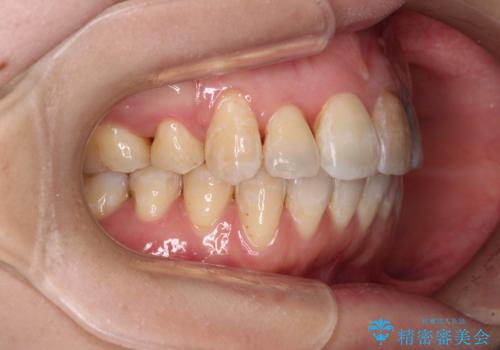

内側に転位していた歯はきれいに歯列に収まり、清掃性が著しく改善しました。

元々神経の失活してしまっている前歯2本は変色が目立つようになってきたため、今後セラミッククラウンによる補綴治療を行う予定です。